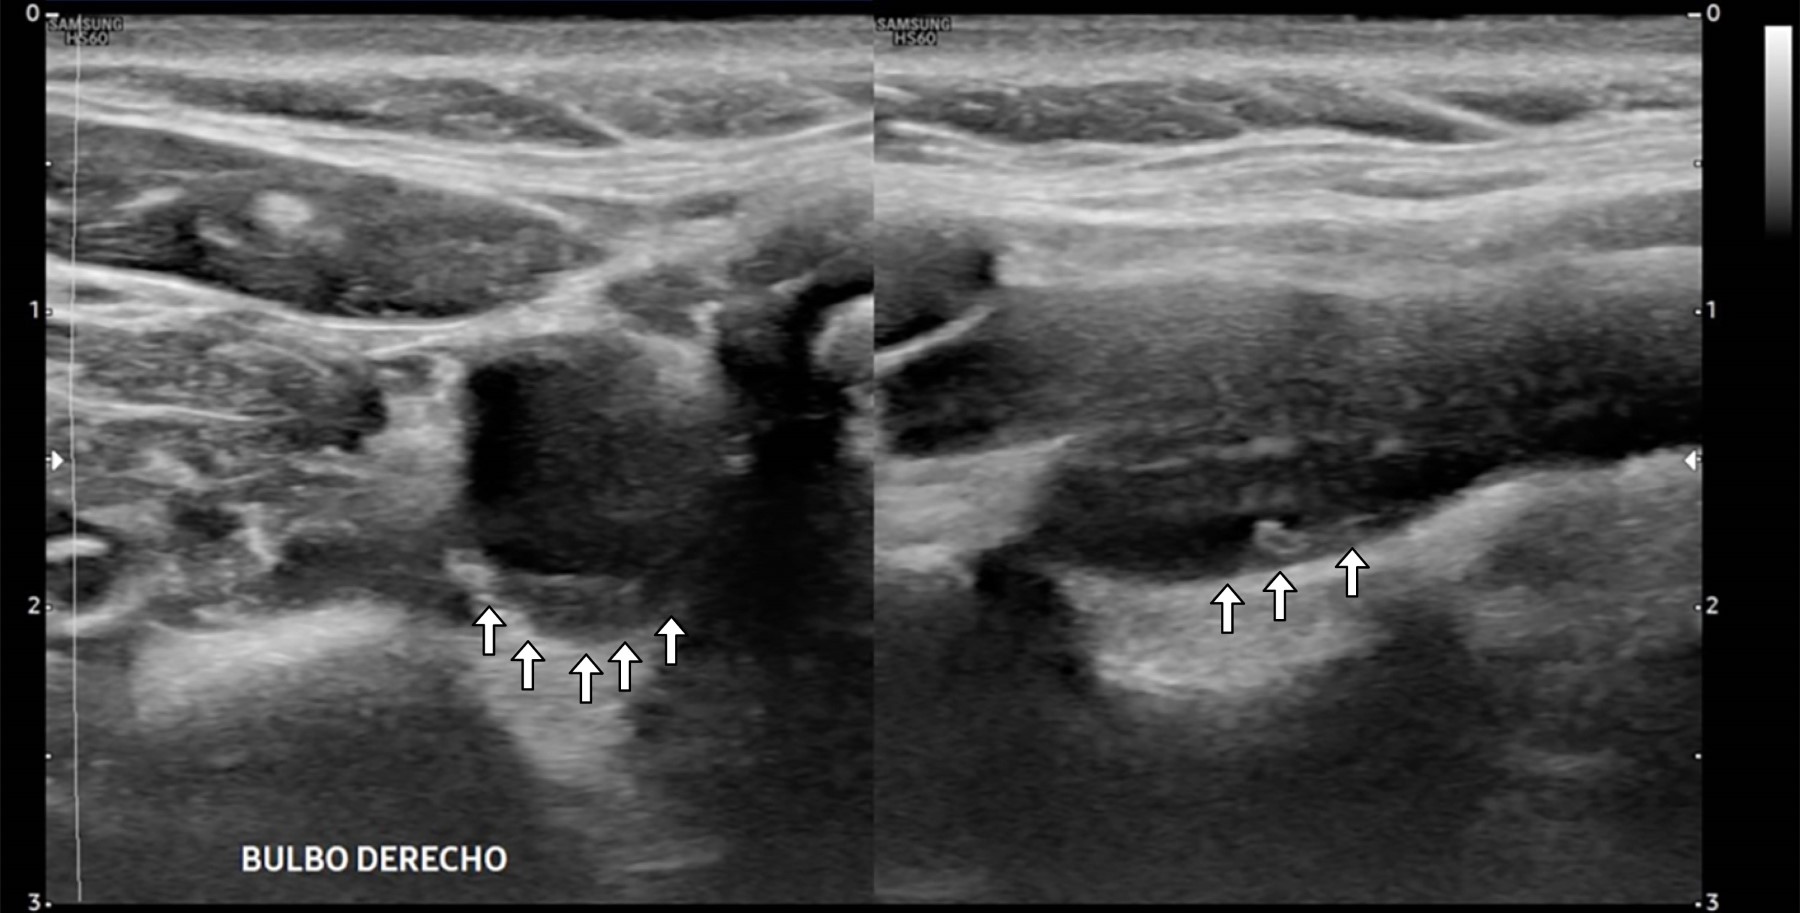

Femenino de 40 años con ataque isquémico transitorio (AIT), en la que se efectuó ultrasonido y angiotomografía que mostraron banda carotídea ipsilateral. La displasia fibromuscular atípica del bulbo o banda carotídea es una patología no ateromatosa implicada en la aparición de infartos cerebrales. La banda carotídea se define como un defecto de llenado lineal en forma de estante en la cara posterior del bulbo de la arteria carótida interna mediante angiotomografía (Figura 1) y/o ultrasonido (Figuras 2 y 3), se reconoce cada vez más como una causa de accidente cerebrovascular criptogénico y/o AIT recurrente, pero la evidencia sigue siendo escasa. Se observa en ambos géneros, con distribución 2:1 a favor del femenino y mayor incidencia en personas de color; cuando son bilaterales (60%) presenta mayor longitud en el lado ipsilateral sintomático que en el contralateral (3-4.5 mm vs 1.85-2.9 mm), observando trombos superpuestos hasta en 30% de los casos con banda carotídea sintomática. A pesar de la recurrencia y gravedad de los accidentes cerebrovasculares originados por embolización asociada con banda carotídea, no existen recomendaciones sobre la mejor estrategia para su manejo; el tratamiento con agentes antiplaquetarios previene la aparición de accidentes cerebrovasculares, pero el tratamiento radical sigue siendo quirúrgico y/o endovascular.

Figura 2